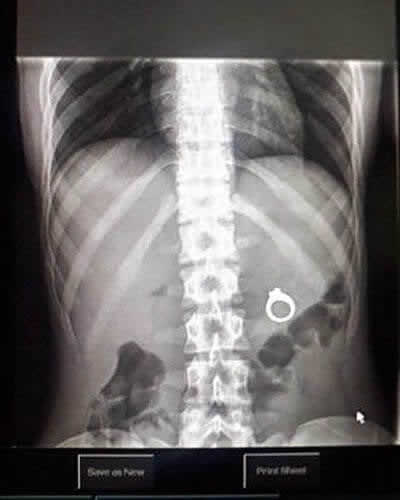

Une bague au mauvais endroit

Les urgences sont toujours pleines de surprises. Les professionnels de la santé ont tout vu, et la machine à rayons X ne ment jamais. Il est vraiment choquant de voir ce que les gens parviennent à avaler ou à se coincer dans leur corps. Cette image montre une bague de fiançailles logée profondément à l’intérieur d’une patiente. Comment elle a fini près de ses organes internes est un mystère pour l’éternité !

Cela semble être une demande en mariage qui a mal tourné. Le partenaire a probablement caché le bijou dans une boisson ou un repas, et elle l’a avalé accidentellement. Espérons que les chirurgiens ont réussi à récupérer la gemme sans encombre !